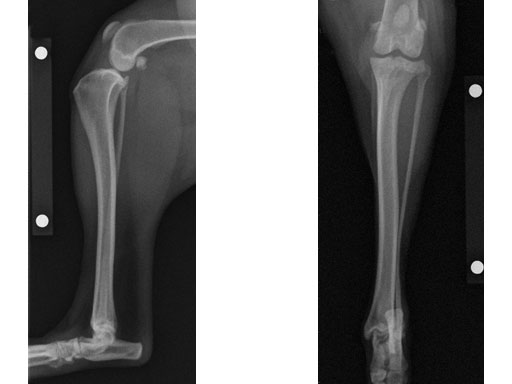

(Case provided by Brian Beale, Houston, USA)

An 8-year-old, female, spayed, 24 kg Australian cattle dog. This breed has short stocky legs and is very energetic and strong. The added strength of the 3.5 mm plate over the TPLO 2.7 mm plate was an advantage. The smaller head profile and shorter length of the TPLO 3.5 mm small stature plate allowed it to fit nicely on this patient.